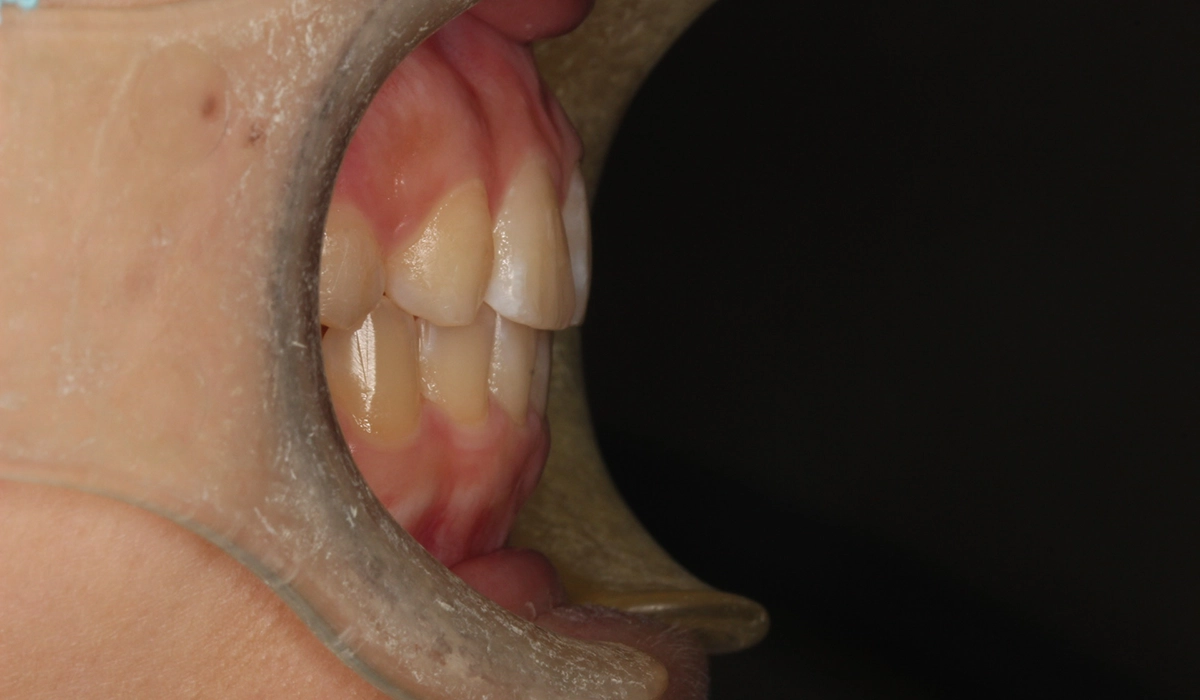

術前:右側

術後:右側